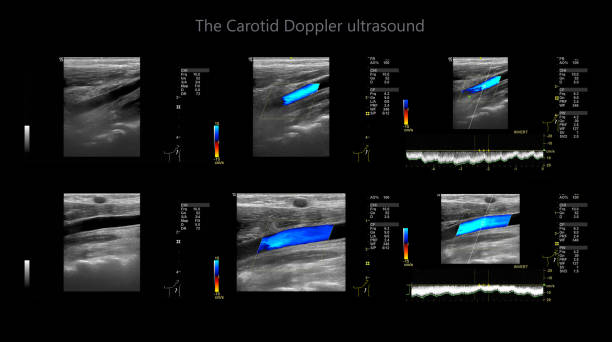

경동맥 초음파 검사의 원리

경동맥 초음파 검사는 초음파 기계를 사용하여 경동맥의 상태를 확인하는 검사입니다. 이 검사는 무해하고 비침습적이며, 빠르게 수행할 수 있어 환자에게 불편함을 주지 않습니다. 검사 과정은 다음과 같습니다.

- 초음파 프로브는 고주파 소리파장을 방출하여 경동맥의 이미지를 생성합니다.

- 이미지를 컴퓨터 모니터에 표시하여 의사가 경동맥의 상태를 시각적으로 확인할 수 있습니다.

경동맥 초음파 검사로 알수있는병 - 검사 결과 해석

검사 결과를 해석할 때, 의사는 다음 사항을 고려합니다.

- 경동맥의 크기와 형태: 경동맥이 충분히 넓고 매끄럽게 유지되는지 확인합니다.

- 혈류 속도: 혈액이 경동맥을 흐르는 속도를 측정하여 혈액순환에 이상이 없는지 확인합니다.

- 혈액 응고물질의 존재: 콜레스테롤과 혈액 응고물질이 경동맥 벽에 쌓여 있는지 확인합니다.